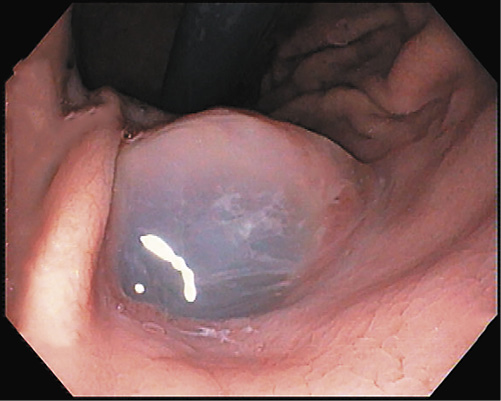

A presumptive diagnosis of disconnected MPD with a gastric fistula due to previous cystic drainage was made, but endoscopic ultrasound (EUS) was performed to exclude a main-duct intraductal papillary mucinous neoplasm (MD-IPMN). Endoscopically, a fistulous orifice 10 mm wide in the gastric antrum was apparent (Fig. 1), with a gelatinous, high-viscosity content which could not be removed despite vigorous lavage. A gastroscope was used to intubate the fistulous tract, but progression was not possible due to the viscous content. The EUS showed a globally dilated MPD (40 mm in the body) with a loss of interface with the gastric wall in the isthmus, 10 mm in diameter (Fig. 2). Fine-needle aspiration (FNA) of the MPD with a 19-gauge needle was performed, revealing a very thick mucinous content. Cytologic analysis confirmed high-grade IPMN, and the patient was referred to surgery (Fig. 3).